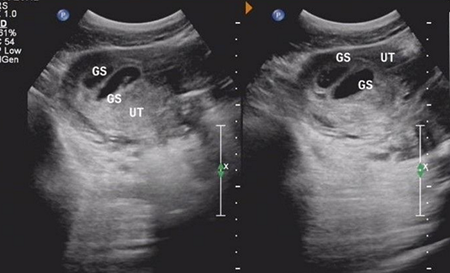

移植34天孕囊多大正常

移植34天相当于怀孕了51天到54天左右,即刚怀孕7周-8周的样子,如果移植的是3天鲜胚,那么就是怀孕51天,如果是移植的5天的囊胚就是54天。

怀孕54天孕囊大小标准介绍

此时的胎儿长到1.66厘米,胎形已定,可分出胎头、体及四肢,胎头大于躯干。B超可见胎囊约占官腔1/2,胎儿形态及胎动清楚可见,并可看见卵黄囊。